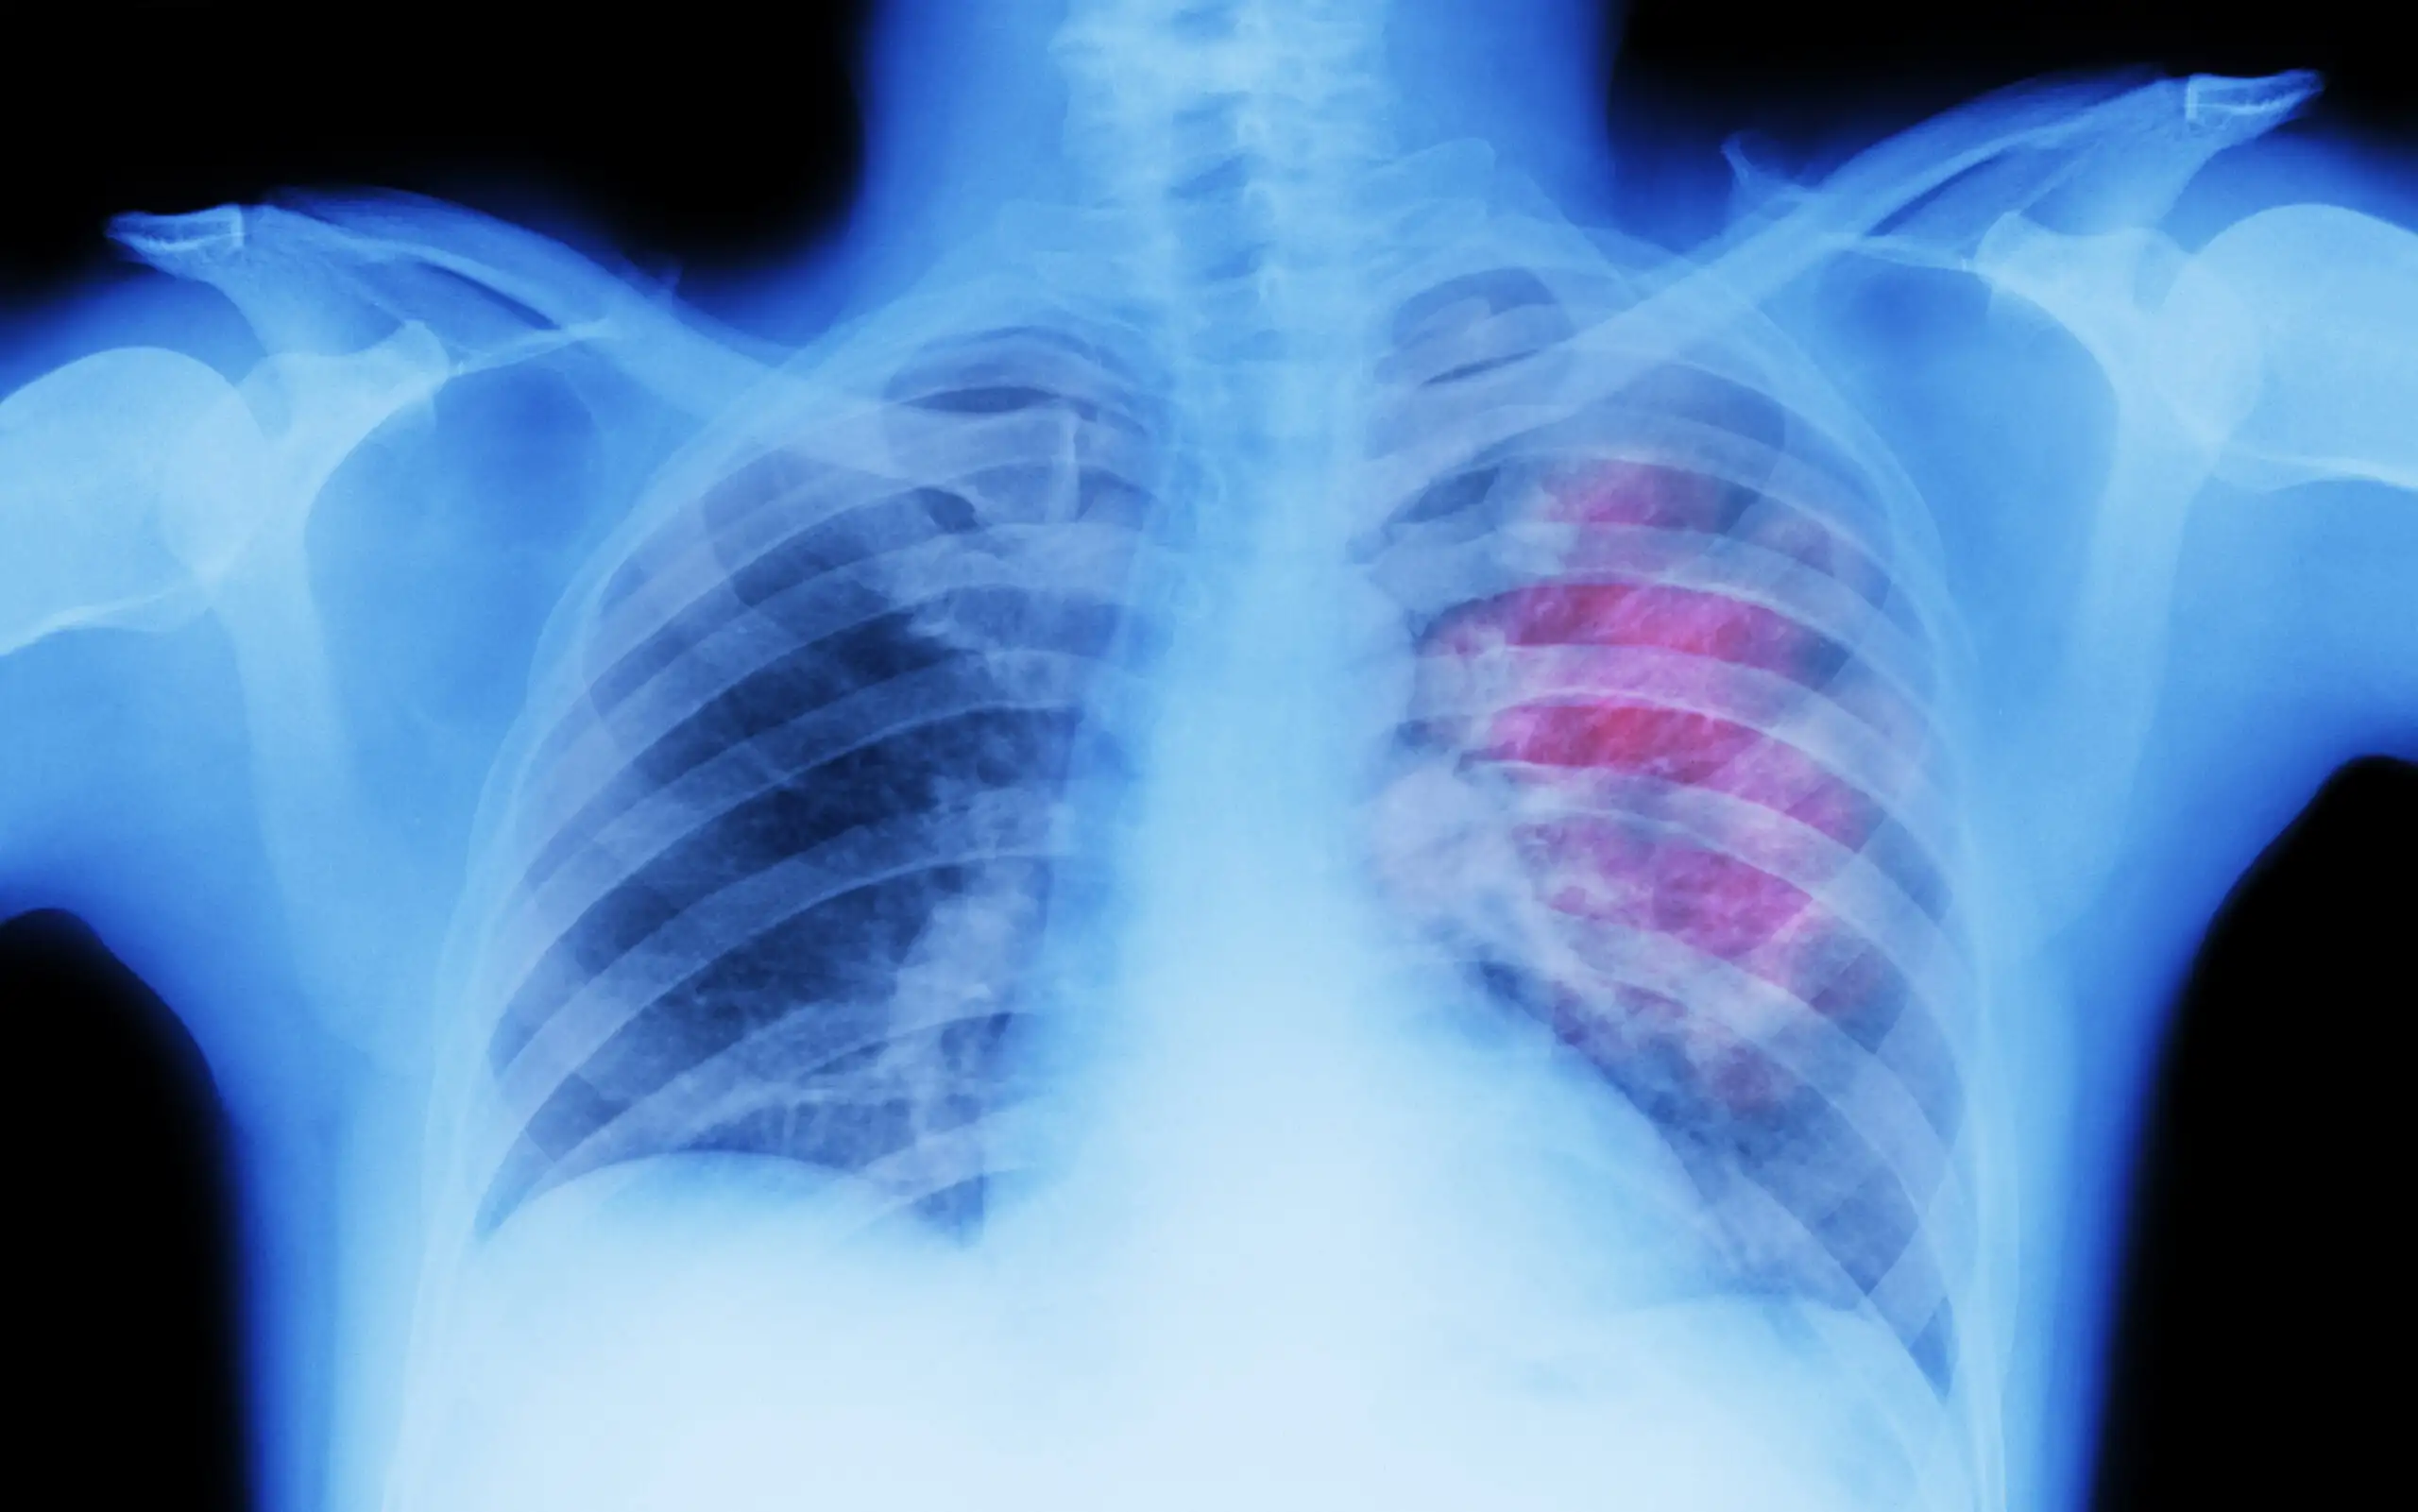

肺がんは日本におけるがん死亡原因の上位を占める重大な疾患であり、その中でも肺がん ステージ 4は最も進行した段階を指します。ステージ4と診断されると、多くの患者さんやご家族が強い不安を感じますが、近年は医療の進歩により治療選択肢が大きく広がっています。分子標的治療薬や免疫チェックポイント阻害薬の登場により、従来よりも長期生存が期待できるケースも増えています。…

肺がんは、日本におけるがん死亡原因の上位を占める重大な疾患です。特に「肺がん 症状」は初期段階では目立ちにくく、風邪や気管支炎と誤認されやすいことから、発見が遅れるケースも少なくありません。そのため、早期警告サインを正しく理解し、適切なタイミングで医療機関を受診することが極めて重要です。…